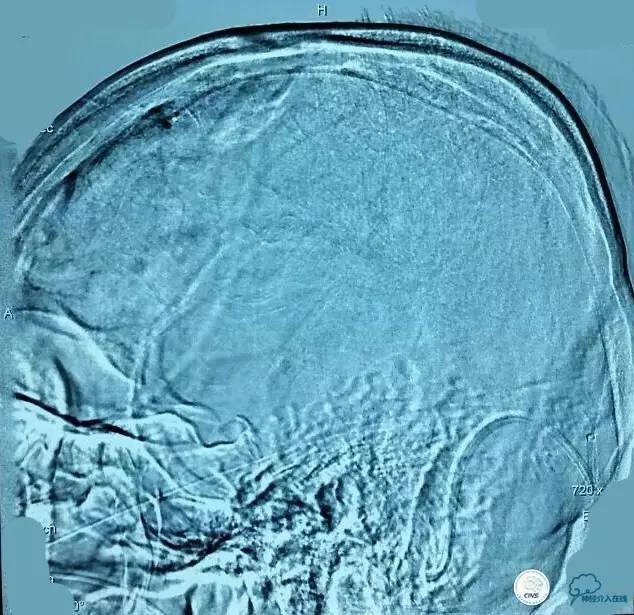

▼第三次取栓后造影,窦通畅,下矢状窦显影延迟,说明上矢状窦通畅了。